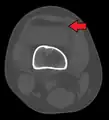

Lipohemarthrosis (presence of fat and blood from bone marrow in the joint space after an intraarticular fracture) seen on X-ray in a person with a subtle tibial plateau fracture

Lipohemarthrosis due to a tibial plateau fracture

3D reconstruction of a CT image of a tibial plateau fracture